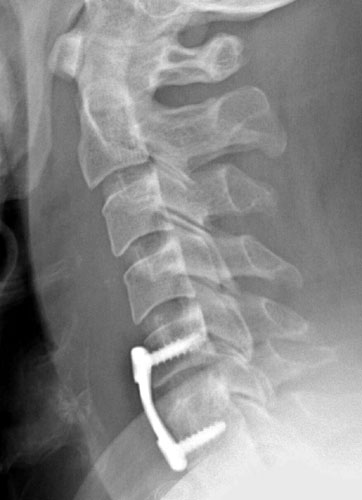

Lateral radiograph taken 1 day after surgery. The cortical screws and the anterior plate appear well seated. There is prevertebral soft tissue swelling, consistent with the recent surgery.